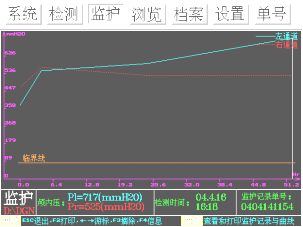

入院第1天使用重庆海威康医疗仪器有限公司无创颅内压监测仪检查患者颅内压,提示双侧颅内压增高,分别为右侧462mmH2O、左侧372 mmH2O,4h后复查右侧567mmH2O、左侧549mmH2O,第2天复查右侧525mmH2O、左侧585mmH2O,因患者临床症状好转,而无创颅内压检测提示颅内压呈持续上升状态,故引起临床重视,第3日患者症状突然加重,复查头颅CT提示“左侧颞叶大面积脑梗死,中线移位”(见图1)。此时复查无创颅内压检测:分别为右侧525mmH2O、左侧717mmH2O,双侧压力差>150mmH2O,提示脑疝可能(见图2)。之后转脑外科行手术减压治疗。起病后无创颅内压检测提示颅内压逐渐增高,并有脑疝趋势(见图3),为疾病的及时诊断提供了帮助。

图3:颅内压监测趋势图